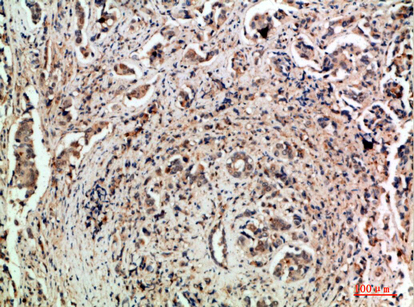

TLE1/2/3/4 (Transducin-Like Enhancer of Split 1/2/3/4) antibodies target members of the TLE protein family, which function as transcriptional corepressors involved in developmental regulation and oncogenesis. These proteins are homologs of Drosophila Groucho, sharing a conserved N-terminal Q domain and WD40 repeats for protein interactions. TLE proteins lack DNA-binding domains but modulate gene expression by interacting with transcription factors like HES1. RUNX, and TCF/LEF, thereby regulating Notch, Wnt, and other signaling pathways. Their roles span cell differentiation, apoptosis, and epigenetic regulation via histone deacetylase (HDAC) recruitment.

In diagnostics, TLE1 is a well-established immunohistochemical marker for synovial sarcoma, with nuclear staining aiding its distinction from other soft tissue tumors. TLE2 and TLE4 are less characterized but implicated in hematopoiesis and immune responses. TLE3 has gained attention in oncology for its potential association with chemotherapy response, particularly in gynecological cancers, though evidence remains inconclusive. Commercially available antibodies vary in specificity; cross-reactivity between TLE isoforms is a common challenge, necessitating careful validation in research and clinical settings. Recent studies also explore TLE dysregulation in neurodegenerative diseases, expanding their therapeutic relevance.